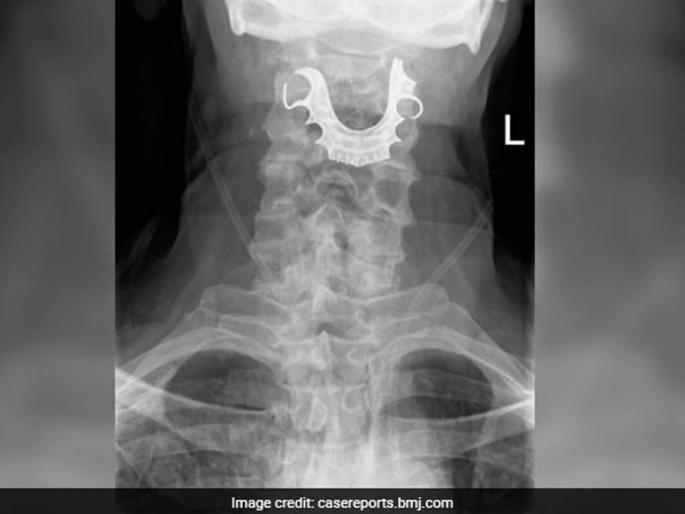

डॉक्टरही ऐकून विचारात पडले. यावेळी डॉक्टरांना वाटलं होतं की, कदाचित इन्फेक्शन झालं असाव. तेव्हा डॉक्टरांनी घशाचीही तपासणी केली. त्यावेळी त्यांना आढळलं की, आजोबांच्या घशात काहीतरी अर्धवर्तुळाकार आकाराचा धातू अडकला आहे. आजोबांना त्याबाबत विचारलं तेव्हा त्यांनी सांगितलं की, त्यांची दाताची कवळी ऑपरेशनच्या दिवसापासून हरवली आहे. डॉक्टरांनी हे ऐकल्यावर चटकन घशाचा एक्स-रे काढला. त्यावेळी जे समोर आलं ते पाहून डॉक्टरही अवाक् झाले होते. आजोबांची हरवलेली कवळी त्यांच्या घशात अडकली होती.